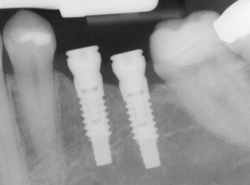

- Computer-Enhanced Treatment Planning: We have special software on our computer that allows us to evaluate your dental CT scan in three dimensions for bone quality, bone quantity, and bone location, enabling the best possible placement of your dental implants. This also allows us to work closely and smoothly with your restorative dentist to ensure an ideal result where your dental implants are concerned.

To make the new tooth or teeth, your dentist will make an impression of your existing teeth, creating a model of your bite. The new restoration, most typically a crown, will be based on this model so it will blend in perfectly with the rest of your teeth. The crown is then attached to the connector point (abutment) on your implant.